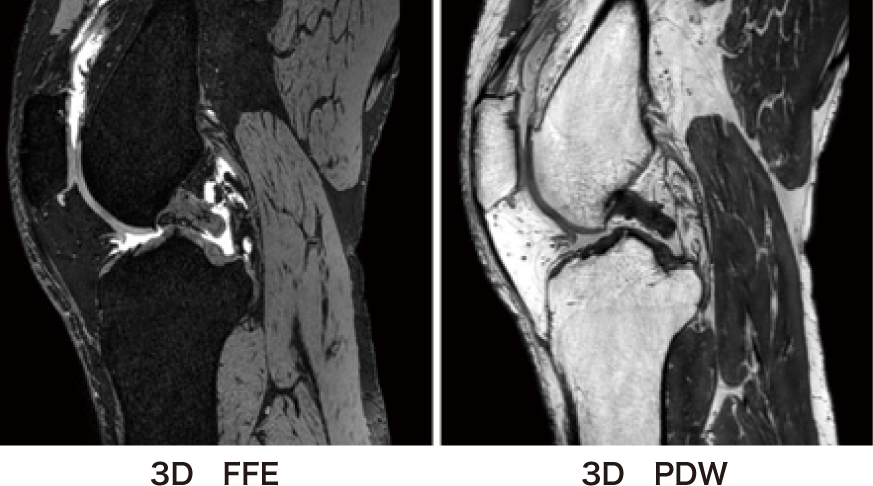

当院での膝関節解析を行うための撮像条件を下記に記す(表1・図3)。

図3